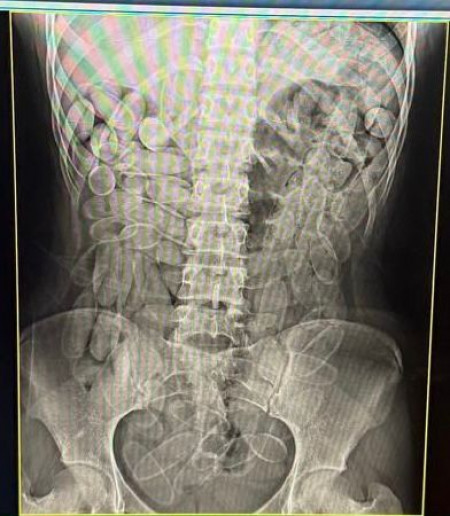

Diante dos fatos, ela foi encaminhada para o hospital, onde passou pelo exame de raio-x, que comprovou a existências de diversas cápsulas no organismo. Pressionadas, as duas confessaram o tráfico de drogas.

A outra jovem também disse ter consumido o material, que totalizou 102 unidades em cada estômago. Ao todo, a apreensão resultou em aproximadamente 2,2 quilos de droga. O destino do entorpecente não foi divulgado.